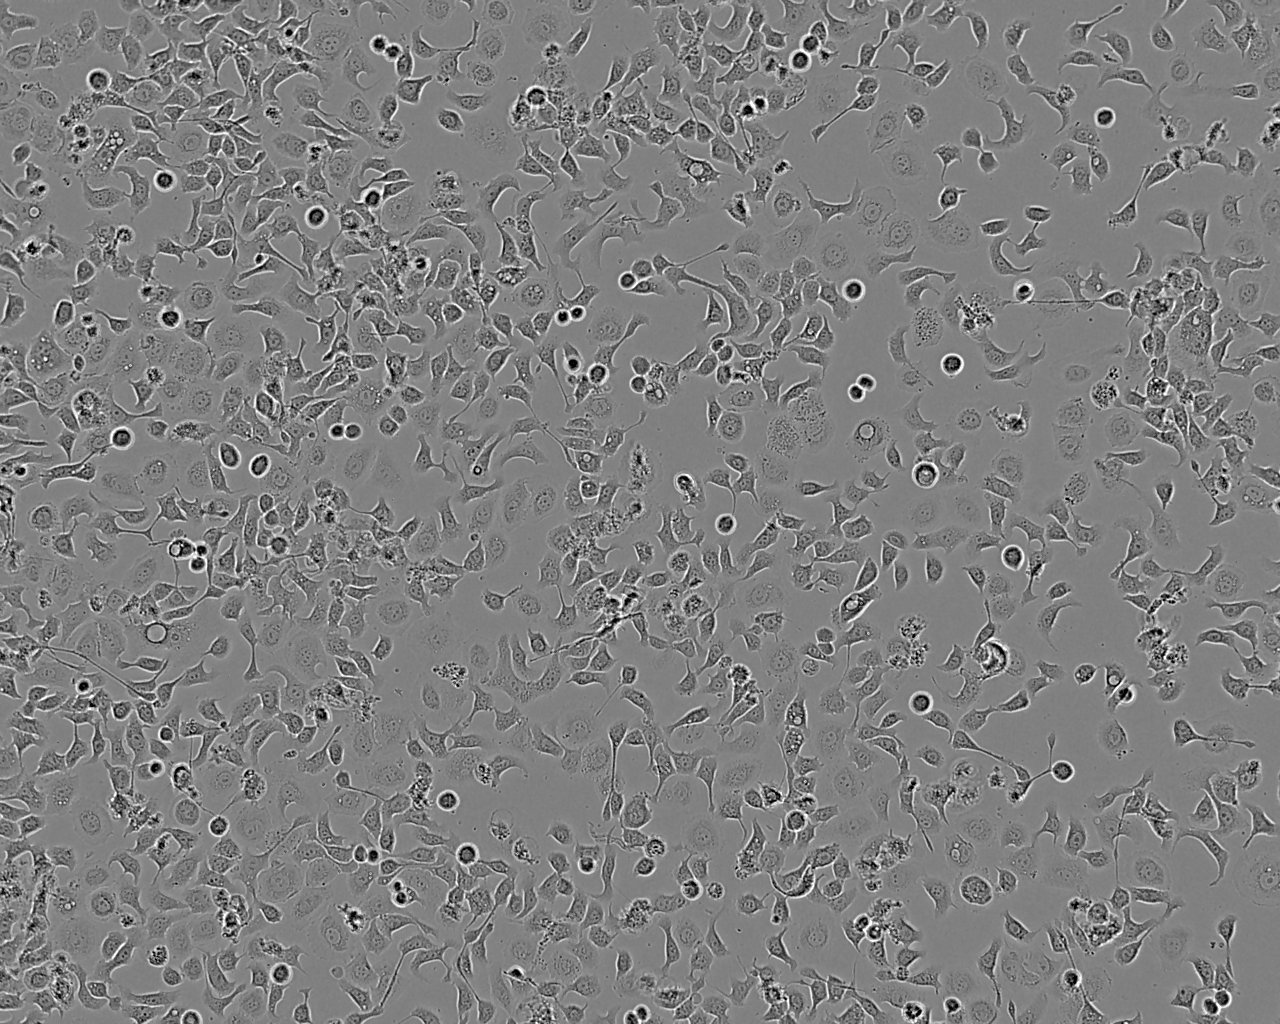

Pleiomorphic - both epithelial and fibroblastoid cells with cytoplasmic protrusions

Adherent